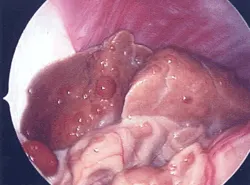

Laparoscopic biopsy from a Labrador retriever dog with copper storage hepatopathy

Third-Tier DiagnosticsLaparoscopic liver biopsies are currently preferred by many internists and surgeons and are considered third-tier diagnostics. Scintigraphy and portograms are other diagnostic modalities that are typically performed at referral centers or teaching hospitals to help diagnose portosystemic vascular abnormalities.

Laparoscopic liver image of a dog with chronic fibrosing lymphoplasmacytic hepatitis (chronic active hepatitis)